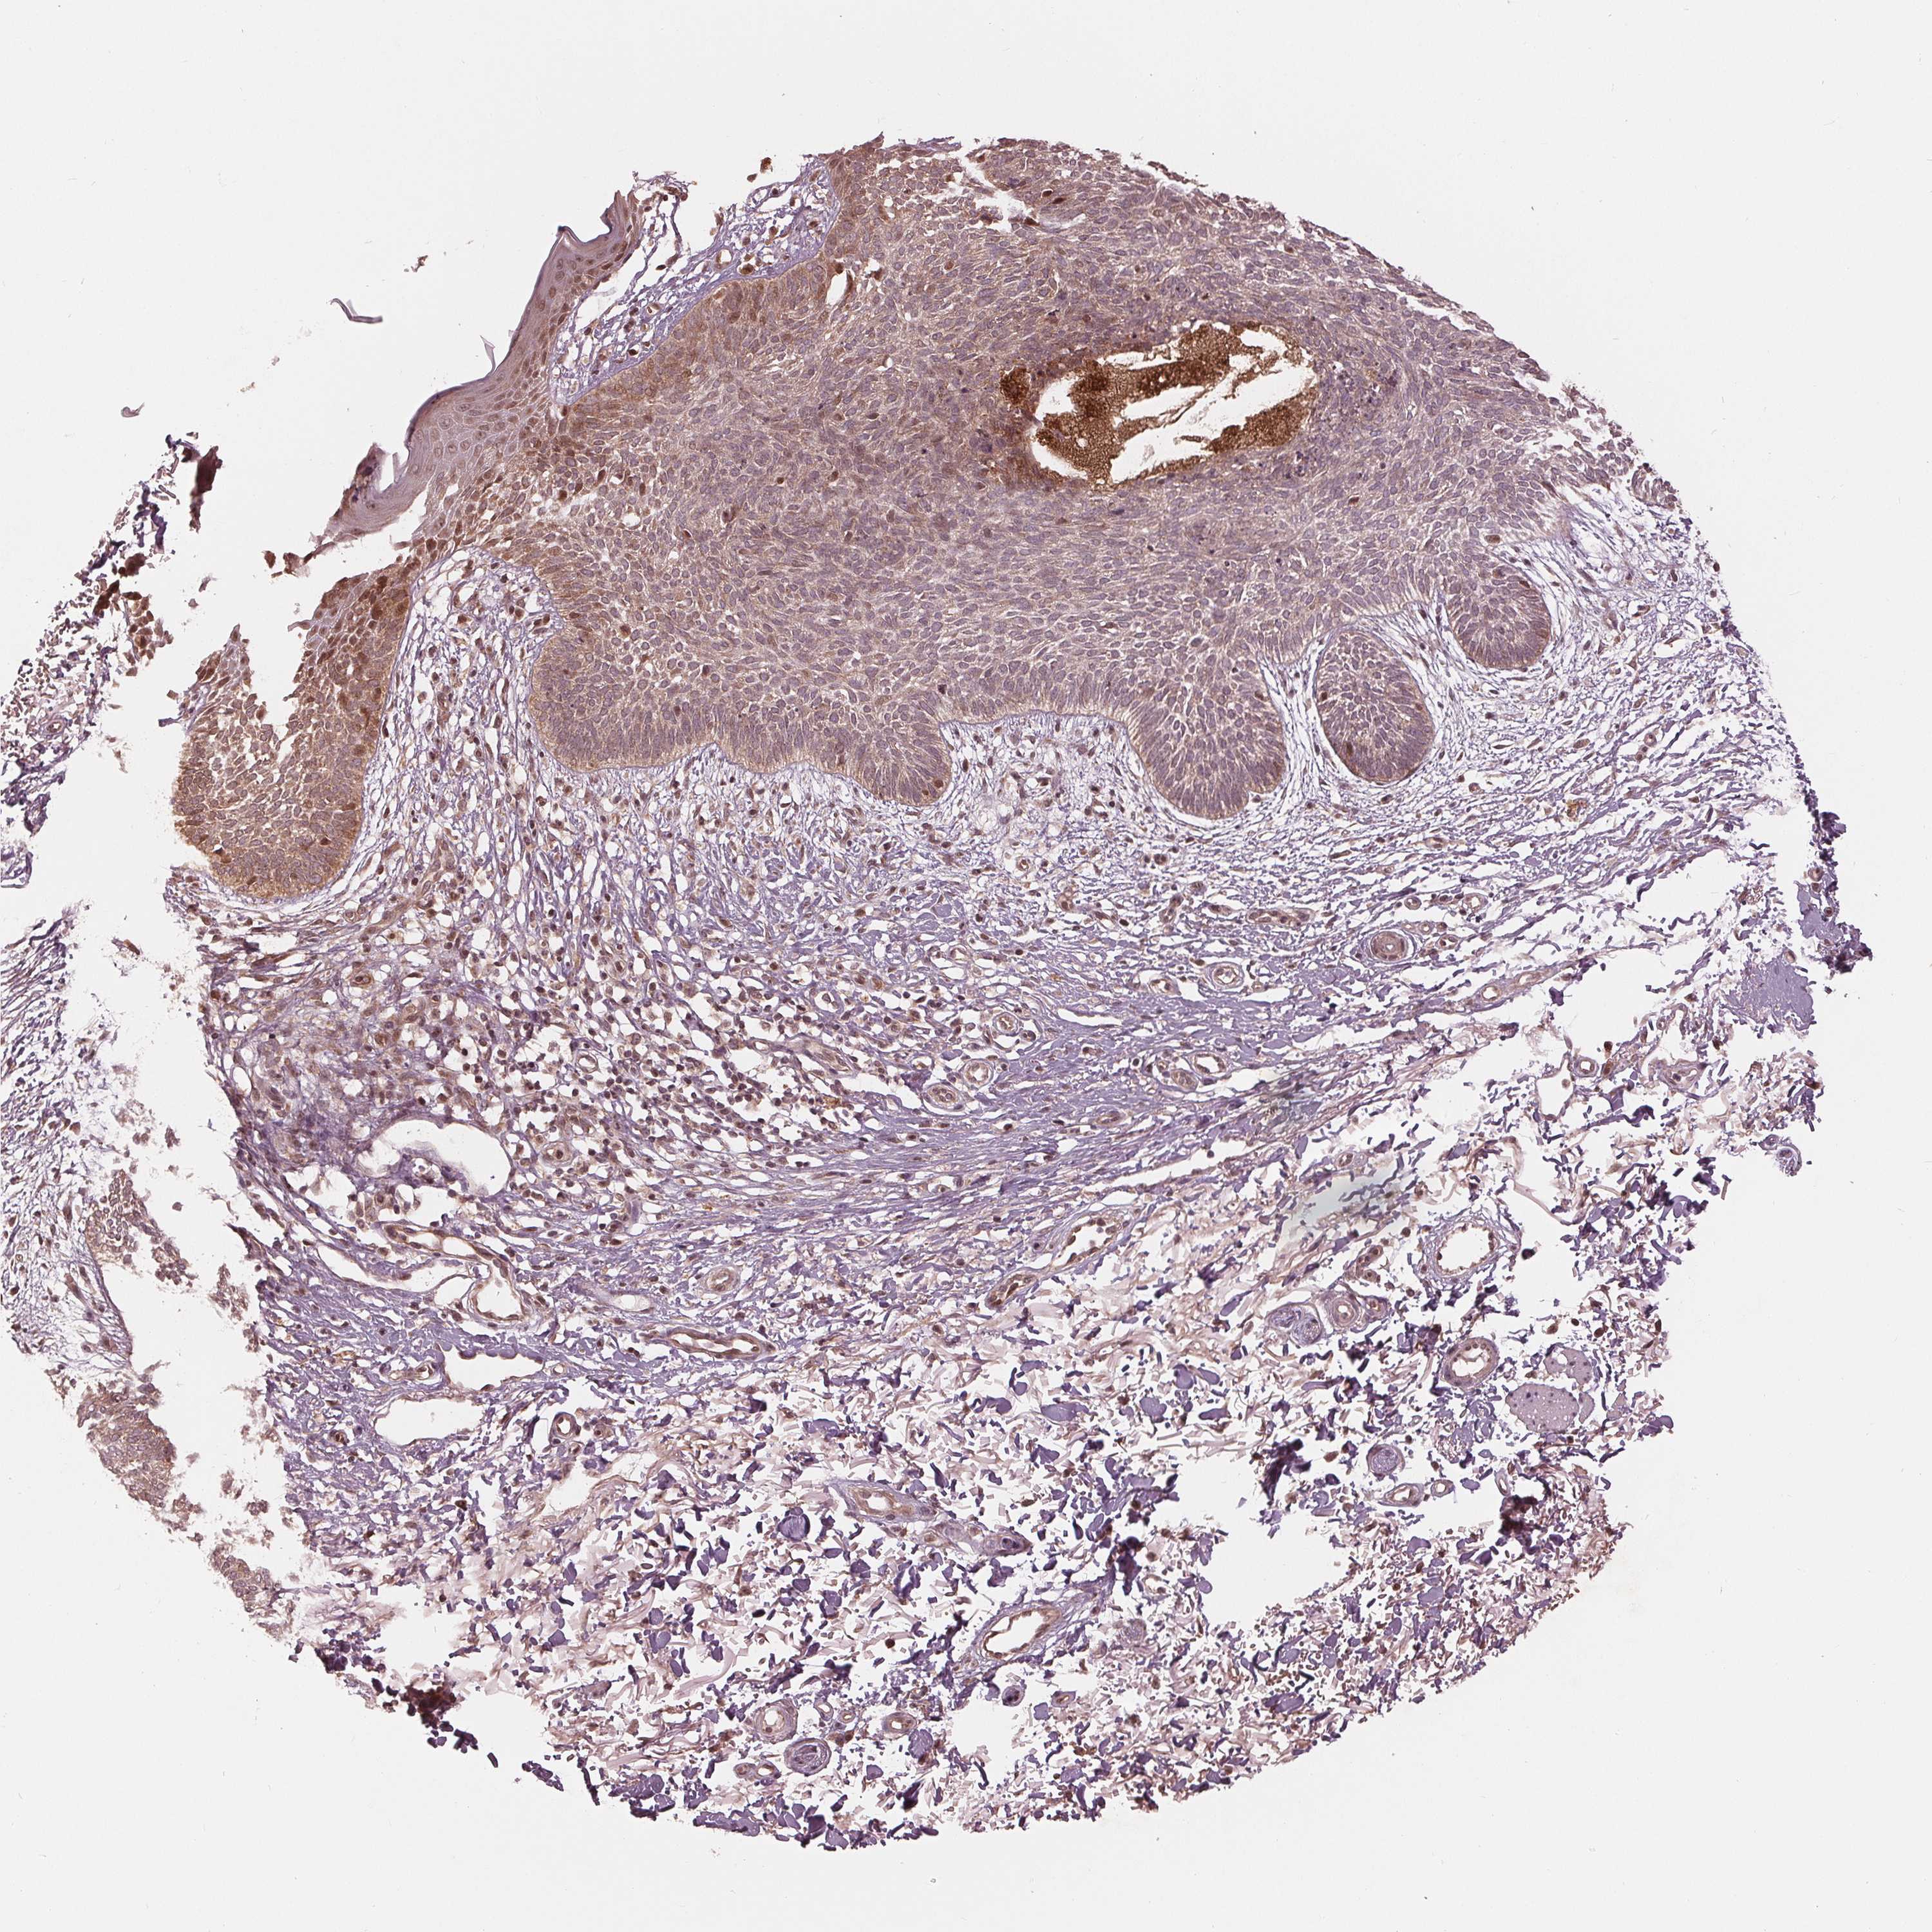

SKIN CANCER - Protein expressioni

A mouse-over function shows sample information and annotation data. Click on an image to view it in a full screen mode. Samples can be filtered based on level of antibody staining by selecting one or several of the following categories: high, medium, low and not detected. The assay and annotation is described here.

Each image is clickable and will lead to virtual microscopy that enables deeper exploration of all samples and also displays staining intensity scores, fraction scores and subcellular localization as well as patient and tissue information for each sample.

Antibody HPA066695

Staining

High

Medium

Low

Not detected

Intensity

Strong

Moderate

Weak

Negative

Quantity

>75%

75%-25%

<25%

None

Location

Nuclear

Cytoplasmic/membranous

Cytoplasmic/membranous,nuclear

Squamous cell carcinoma, NOS